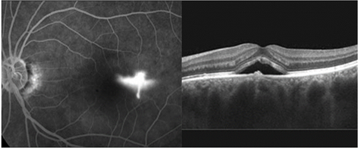

망막 전막의 진단

시력 및 안압검사, 안저검사로 진단 할 수 있으며

자세한 검사를 위해서는 빛간섭단층촬영이 필요합니다.

황반 원공 진단